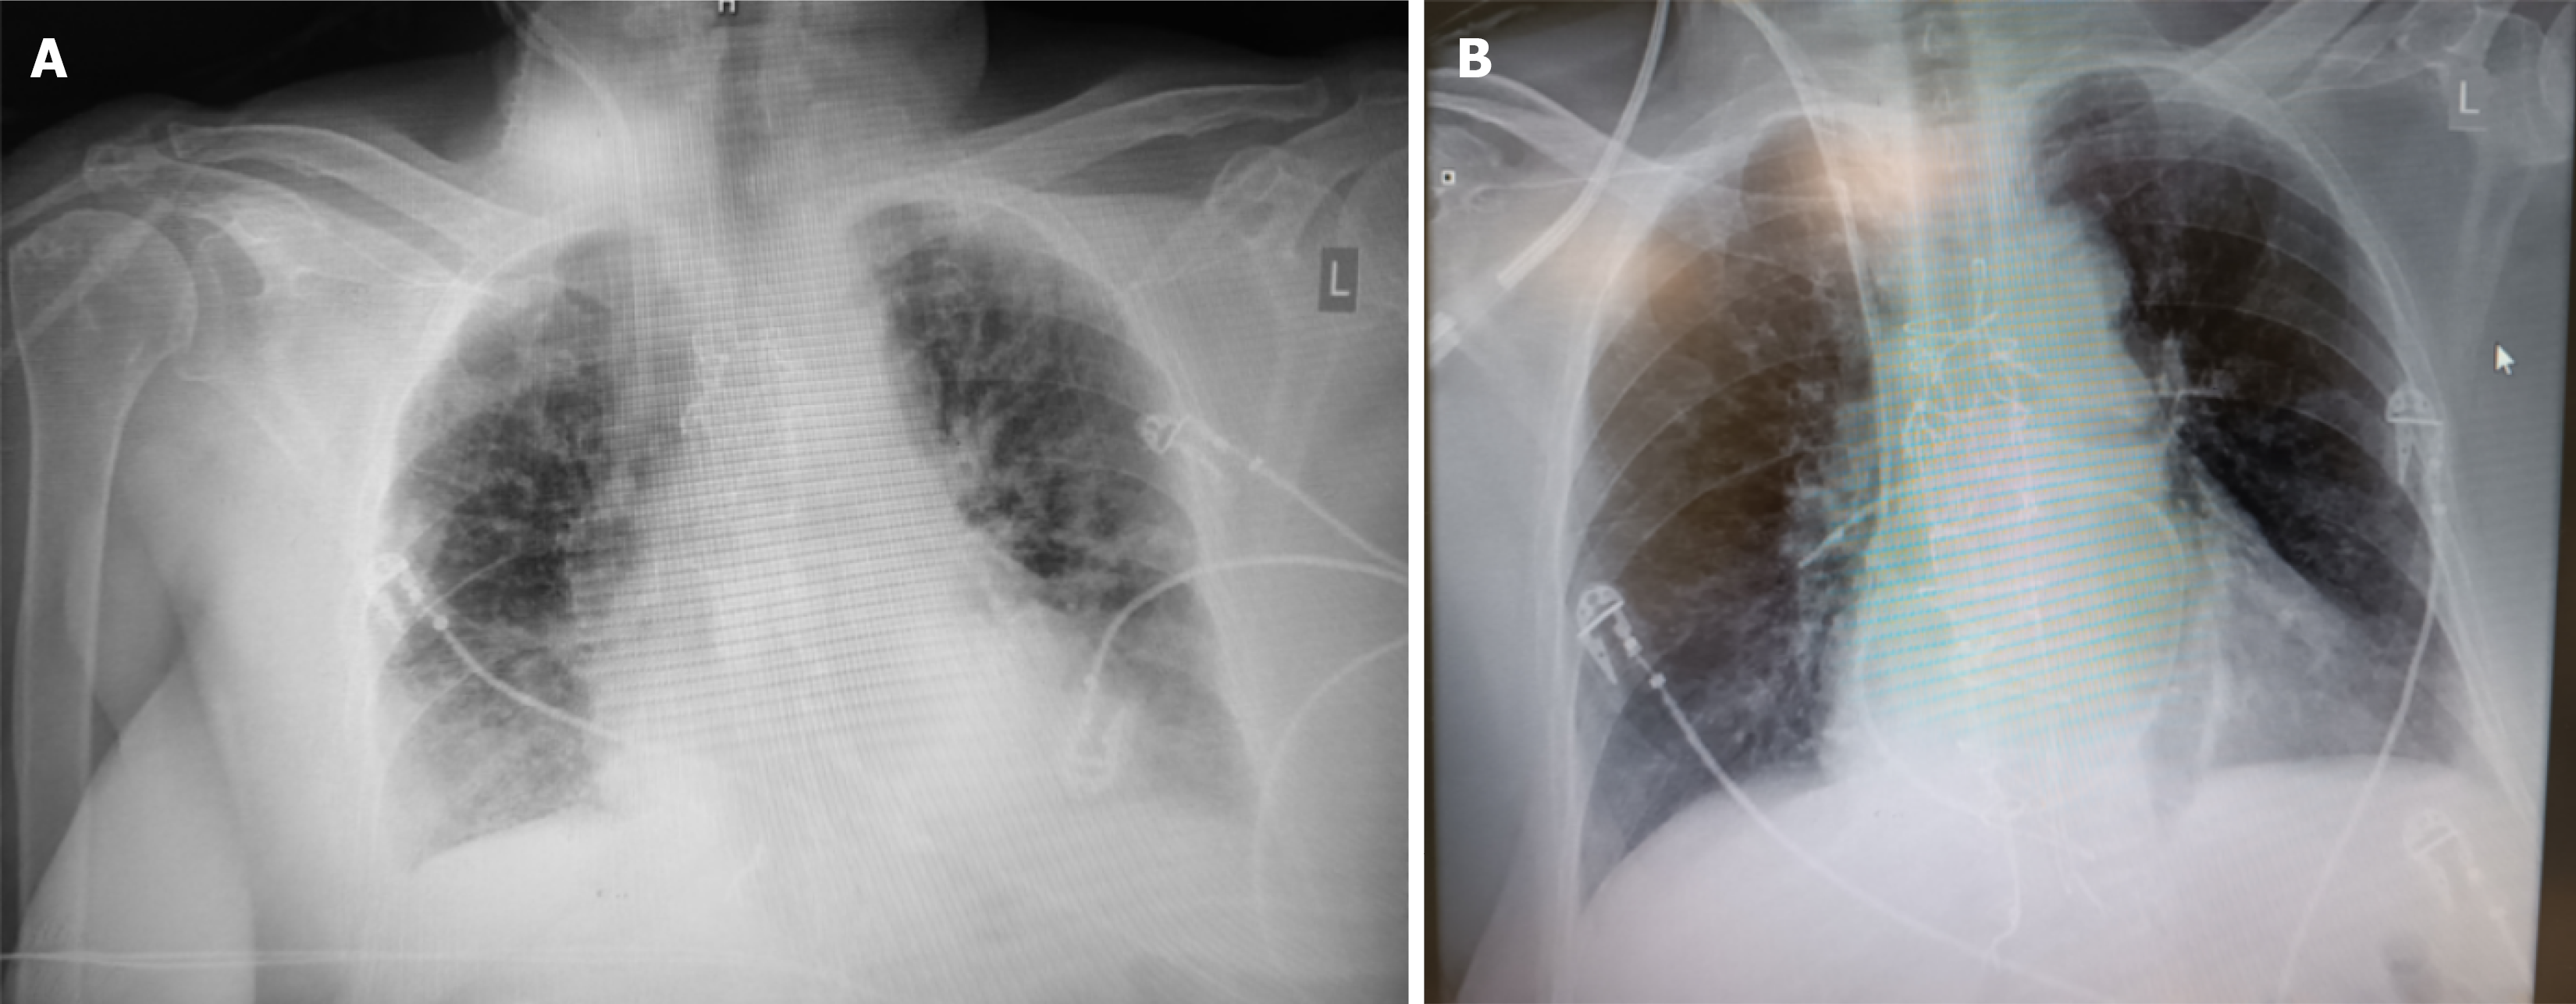

Figure 2 Onset of hypoxemia.

A: Chest X-ray demonstrates pulmonary congestion; B: Resolution of pulmonary congestion on chest X-ray following diuresis and vasopressin.